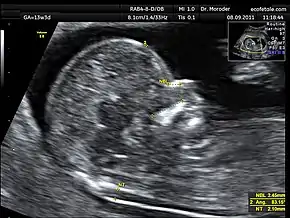

![]() Measurements of fetal nuchal translucency, nasal bone and facial angle according to the standards of the Fetal Medicine Foundation | |

A nuchal scan or nuchal translucency (NT) scan/procedure is a sonographic prenatal screening scan (ultrasound) to detect chromosomal abnormalities in a fetus, though altered extracellular matrix composition and limited lymphatic drainage can also be detected.[1]

There are two distinct measurements: the size of the nuchal translucency and the thickness of the nuchal fold. Nuchal translucency size is typically assessed at the end of the first trimester, between 11 weeks 3 days and 13 weeks 6 days of pregnancy.[3] Nuchal fold thickness is measured towards the end of the second trimester. As nuchal translucency size increases, the chances of a chromosomal abnormality and mortality increase; 65% of the largest translucencies (>6.5mm) are due to chromosomal abnormality, while fatality is 19% at this size.[2] A nuchal scan may also help confirm both the accuracy of the pregnancy dates and the fetal viability.

Procedure

Nuchal scan (NT procedure) is performed between 11 and 14 weeks of gestation, because the accuracy is best in this period. The scan is obtained with the fetus in sagittal section and a neutral position of the fetal head (neither hyperflexed nor extended, either of which can influence the nuchal translucency thickness). The fetal image is enlarged to fill 75% of the screen, and the maximum thickness is measured, from leading edge to leading edge. It is important to distinguish the nuchal lucency from the underlying amniotic membrane.[8]

Normal thickness depends on the crown-rump length (CRL) of the fetus. Among those fetuses whose nuchal translucency exceeds the normal values, there is a relatively high risk of significant abnormality.

How to define a normal or abnormal nuchal translucency measurement can be difficult. The use of a single millimeter cutoff (such as 2.5 or 3.0 mm) is inappropriate because nuchal translucency measurements normally increases with gestational age (by approximately 15% to 20% per gestational week from 10 to 13 weeks).[9] At 12 weeks of gestational age, an "average" nuchal thickness of 2.18mm has been observed; however, up to 13% of chromosomally normal fetuses present with a nuchal translucency of greater than 2.5mm. Thus for even greater accuracy of predicting risks, the outcome of the nuchal scan may be combined with the results of simultaneous maternal blood tests. In pregnancies affected by Down syndrome there is a tendency for the levels of human chorionic gonadotropin (hCG) to be increased and pregnancy-associated plasma protein A (PAPP-A) to be decreased.